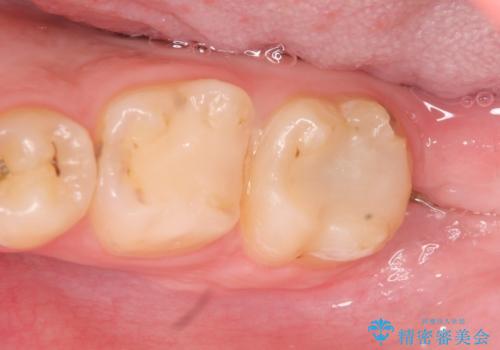

術後歯肉の回復を待ち、左下6はセラミックインレー、左下7はオールセラミッククラウンにて補綴しました。

セラミックインレーについて

当院のセラミックインレーはemaxという強度と審美性に優れた材料を使用しています。

またプレス方式でインレーを製作しているため、削り出しで製作するCADCAMより優れた適合性も持ち合わせており、虫歯が再発しにくい修復物です。

オールセラミッククラウンについて

オールセラミッククラウン(エコノミー)はスタンダード以上と違い、一塊となっているため欠けてしまうリスクが低いのが特徴です。

しかしその反面選択できる色の種類が少なく、色合いも単調であるという欠点もありますが、今回のケースのように前後の歯がクラウンの場合などでは十分に審美的な補綴が可能となります。